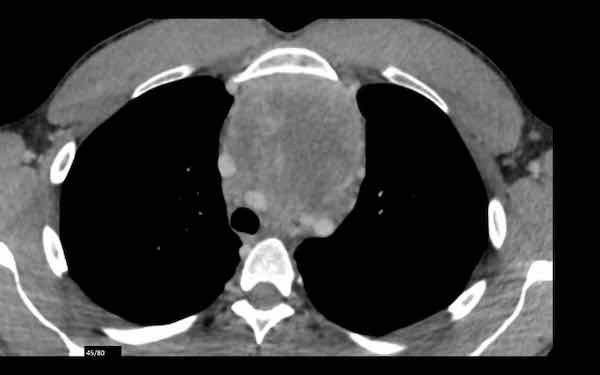

Đây là hình ảnh của một nam giới 24 tuổi.

Hãy quan sát kỹ các hình ảnh trước.

Câu hỏi: đây có phải là tuyến ức bình thường không?

Hình ảnh

Mặc dù tuyến ức này khá lớn, nhưng có hình tam giác bình thường và chứa mỡ (mũi tên).

Đây là tuyến ức bình thường.